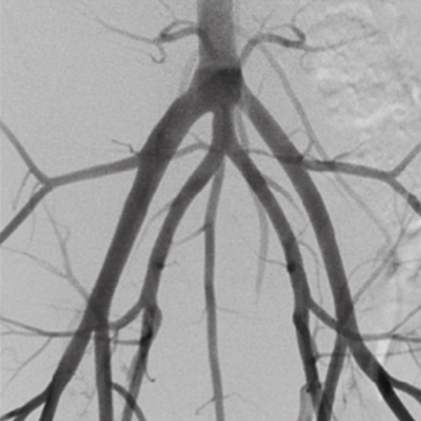

長年の経験により蓄積されたノウハウで卓越した診断映像を提供します。